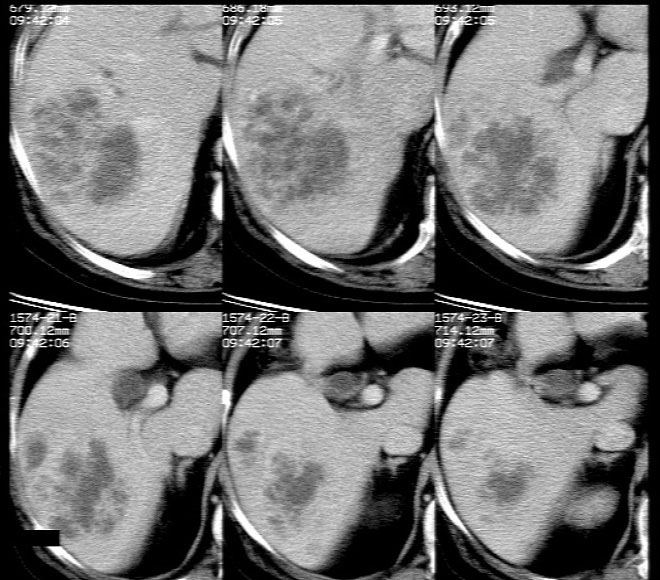

平扫示: 肝右后叶见团状低密度灶,边界欠清,密度略不均匀,ct值28-32hu,肝内胆管无扩张。

ct增强扫描示: 动脉期肝右后叶团状低密度边缘明显不均性强化,内呈不规则峰窝状低密度(无强化区),不规则分隔亦见明显强化;三期扫描像均见,病灶有明显占位征,周围血管、胆管推挤外移,病灶与正常肝组织分界不清,延迟期病灶周围见雾状略低密度(较肝左叶)。

肝右后叶团状低密度占位性病变,结合临床提示: 1、肝脓肿? 2、不排除肝ca可能。建议afp检查。

平扫示肝右后叶见团状低密度灶,边界欠清,密度略不均匀,ct值28-32hu,肝内胆管无扩张。ct增强扫描动脉期肝右后叶团状低密度边缘明显不均性强化,内见多发斑片状无强化液化区,呈不规则峰窝状。

考虑肝脓肿早期(蜂窝组织炎阶段)。

鉴别:肝血管瘤,早期周边强化明显,逐渐向中心充填。原发性肝癌,强化一般呈快进快出,多有乙肝肝硬化病史。